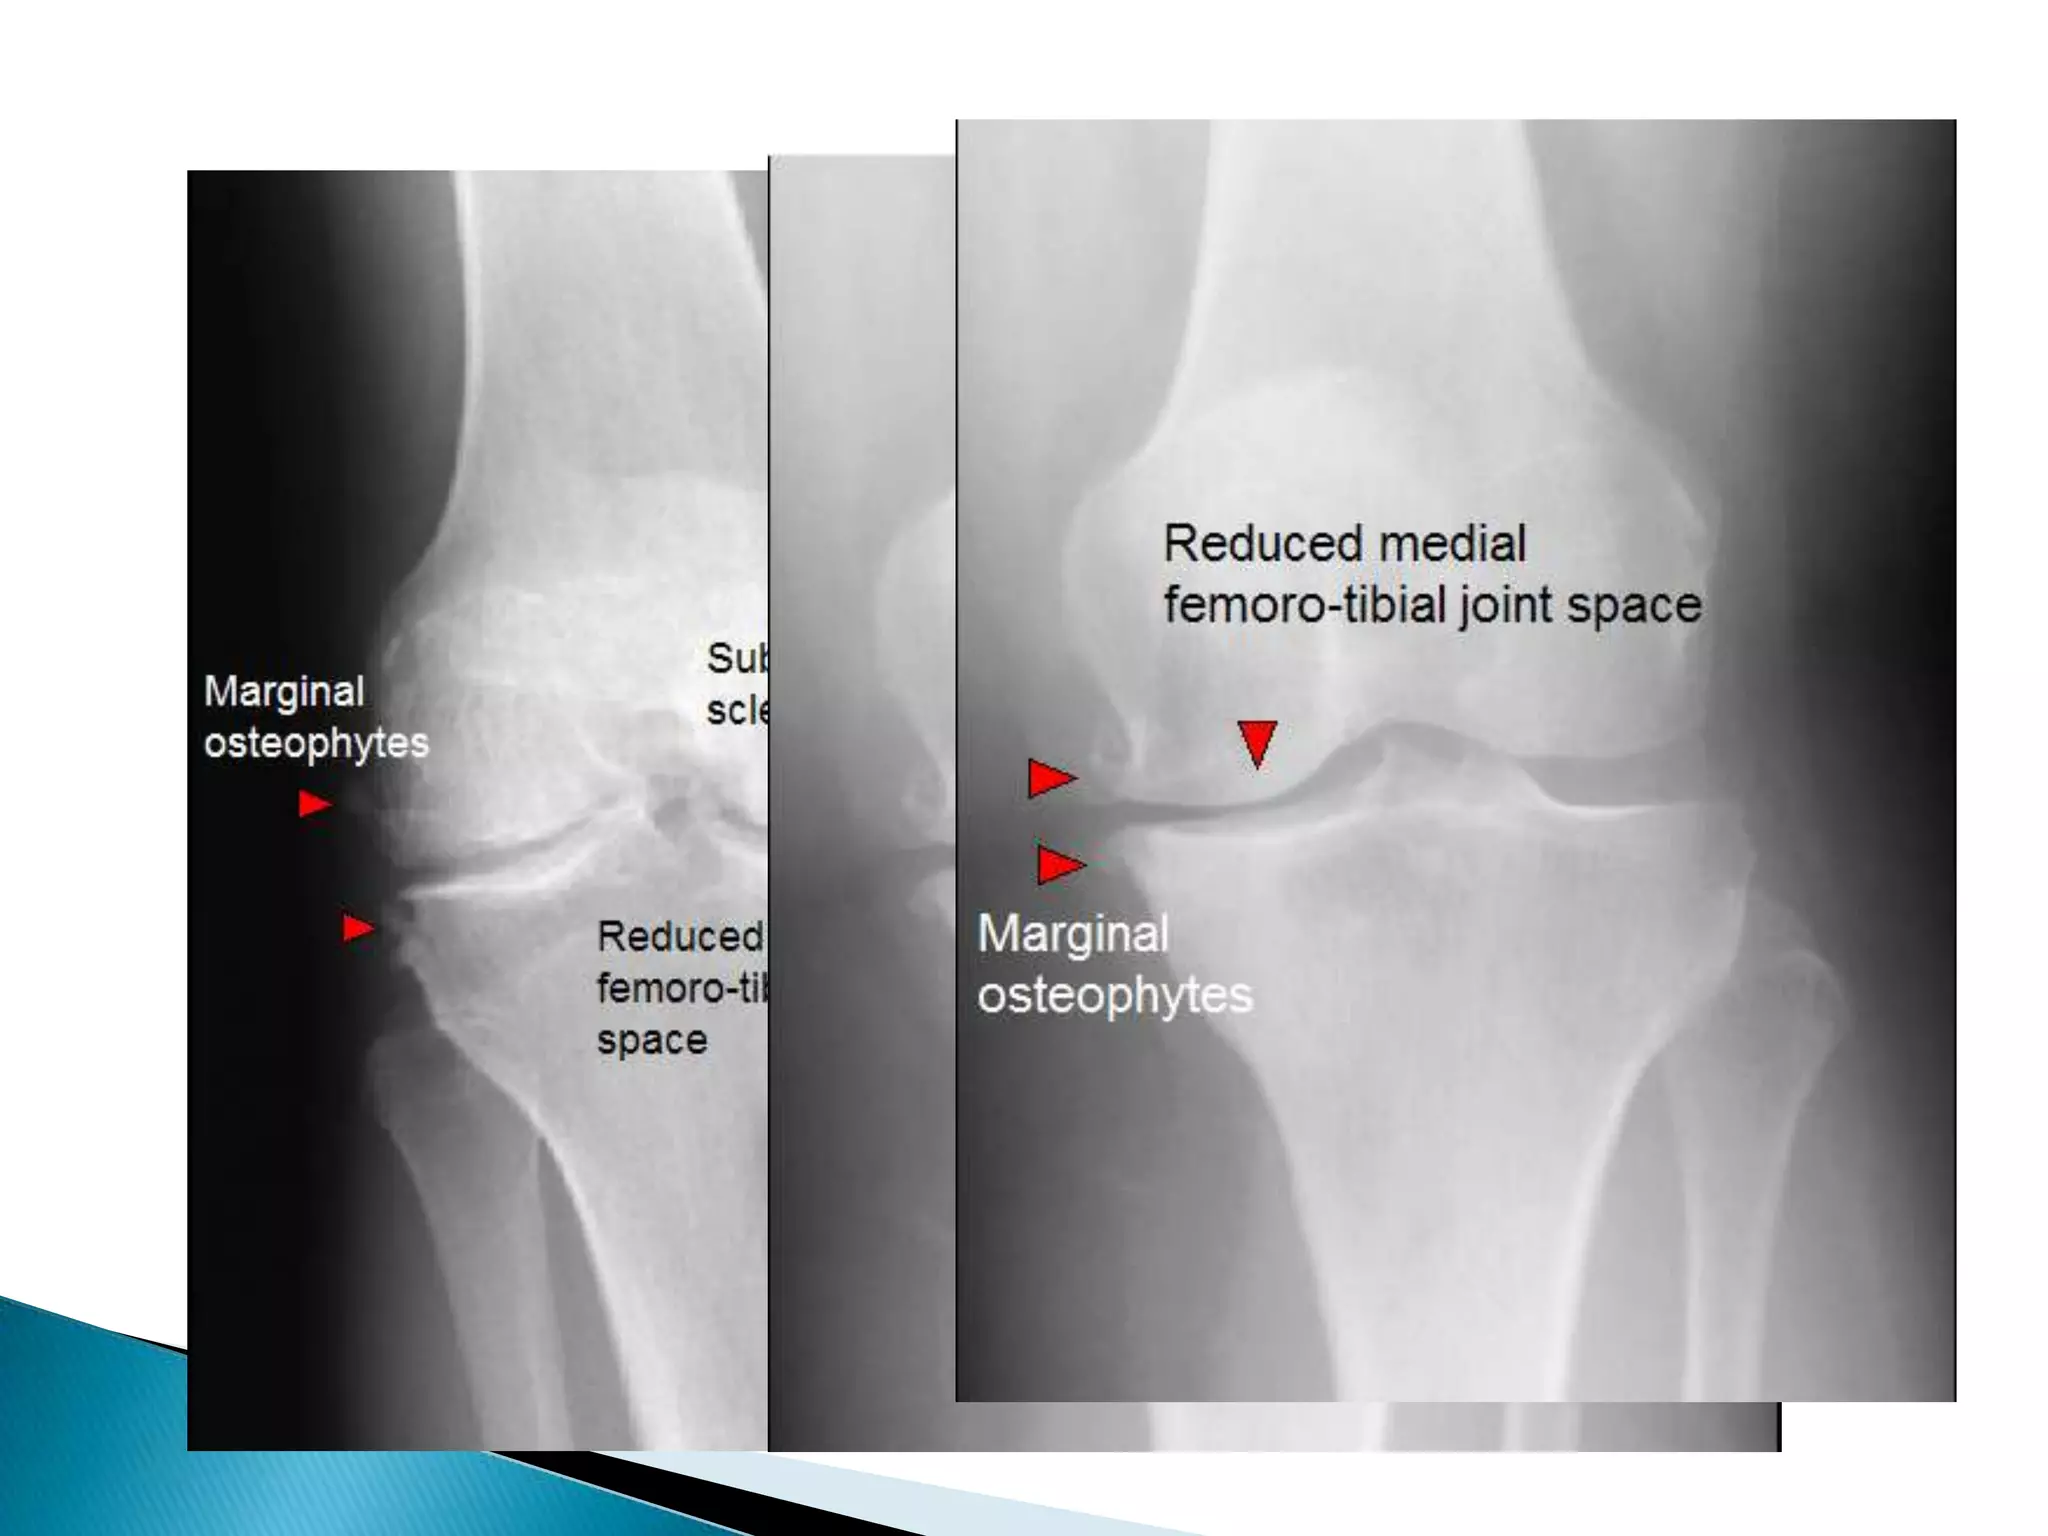

Degenerative arthritis (OA)Is the commonest form of arthritis.Changes occur secondary to wear & tear of the articular cartilage.

OAJoint space narrowed max. at wt bearing site

Erosion do no occur.

Subchondral sclerosis  may be seen.